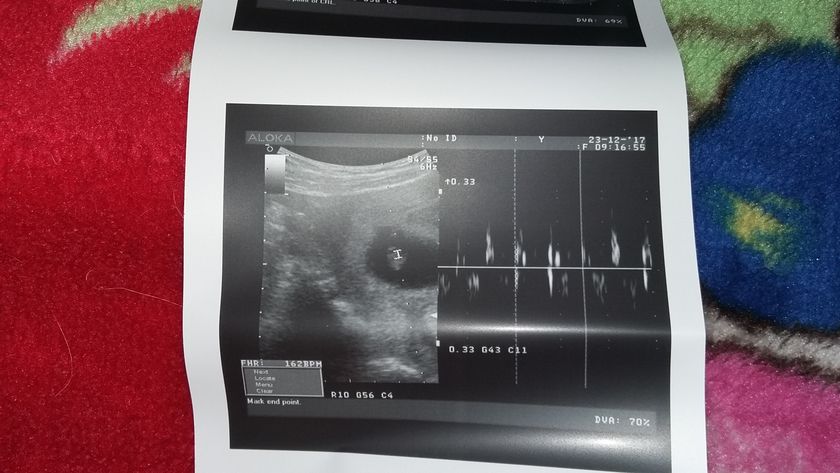

Мои надежды и молитвы все таки сбылись. У второго малыша забилось сердечко??? мои крошечки как же я рада что вы оба живы и здоровы. На данном этапе все хорошо. Один малыш соответствует 7 нед второй 8. Сердечко у одного 163/165 у второго. Конечно узистка мне сказала что это очень сложная беременность. И что гарантий мне никто не даст что все будет хорошо с детками. Но я верю в лучшее. Фото крошек? нафоткала их из разных углов? двоих не смогла поймать

Я вчера тоже была на УЗИ, у нас 169 ударов сердечко и мы уже 19мм???

Здорово???хорошо что все хорошо??? а мы 11 и 13 мм?